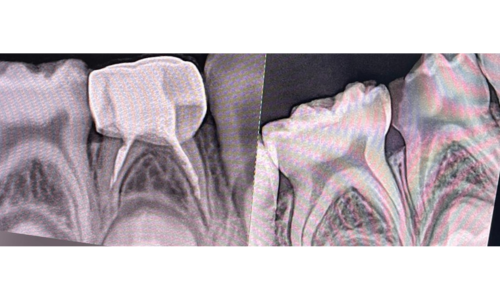

علاج الاطفال